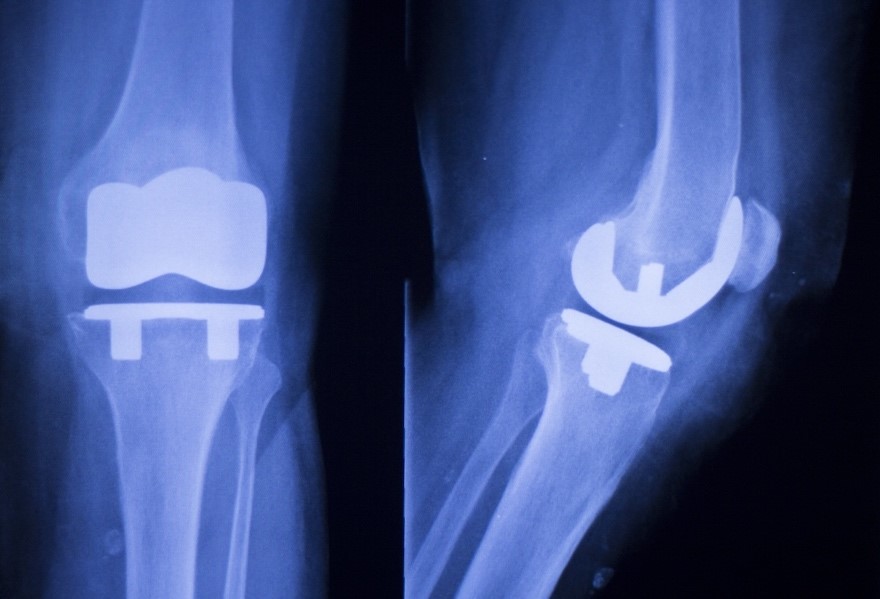

ITHACA, NY (607NewsNow) — Cayuga Medical Center’s orthopedic surgeons are using robotic-assisted technology for total and partial knee replacements and revision knee joint surgery.

The CORI Surgical System provides patients with prosthetic knee replacements that are matched and aligned to their joint anatomy for successful outcomes.

When implants are customized to the patient and placed with precision and accuracy, the patient will walk without pain – often for the first time in years – and the prosthetic joint will have more than a 90 percent chance of lasting 10 or more years. National registries that track replacements show robotic-assisted surgery for knee joint replacement is more accurate than traditional surgery. There is data to suggest there are fewer failures of robotic-assisted knee replacements than with standard replacements. This may reduce failure of the joint and the need for revisions.